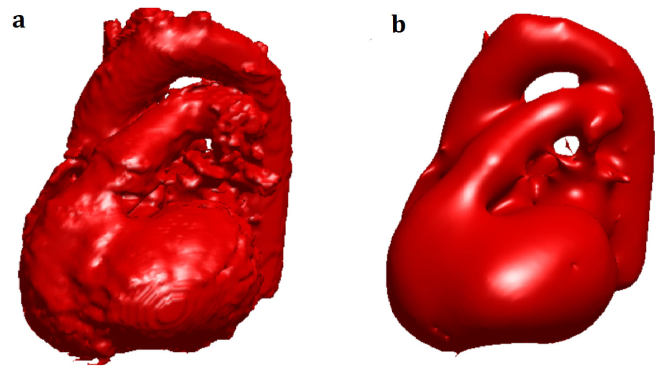

After segmenting the volume of the cardiac structure on each volumetric water image, surface of this volume got computed. This surface was a smoothed 3D (iso)surface555For a continuous function whose domain was the 3D Euclidean space, the isosurface was the set of al 3D points whose values, returned by the function, were a certain constant (isovalue). returned by an enhanced marching cube algorithm [Custodio 2013]. The marching cube algorithm rendered a volume into a 3D isosurface represented by a triangular mesh. That is, it assumed that each piece of the isosurface was a triangle defined by the coordinates of its 3 vertices. Then, it determined the vertices of each triangle by using the cubic patches of the segmented volume. Each patch was represented by its 8 corners’ coordinates and had an intensity at each corner. The isovalue determining the isosurface was defined by the user of the algorithm. The marching cube algorithm compared the intensity of each corner of each patch with this isovalue. If the intensity was higher/lower than the isovalue, then the corner got a 1/0 value. A triangular piece of the isosurface intersected an edge of a cubic patch if the patch’s corners at the two sides of the edge had different values. The location of the intersection was a vertex of the triangle and was determined according to the differences of the intensities of the edge’s corners with the isovalue. That is, the larger the difference of a corner’s intensity with the isovalue was, the further away the vertex from the corner would be [Lorensen 1987].

These issues were tackled by reducing the possibilities of the triangulations in each cubic patch from to 33 cases [Chernyaev 1995, Lewiner 2003]. In [Custodio 2013], these restrictions got enhanced by additionally producing a topologically correct piecewise linear isosurface. Computation of a topologically correct isosurface implied a higher complexity. The method in [Custodio 2013] reduced this complexity by avoiding interpolations at the edges of face or interior ambiguity. The resulting complexity was then linear in the number of triangular pieces (faces) of the triangular mesh of the isosurface. The memory footprint (storage) was also linear in the number of vertices of the isosurface. Thus, we used this method to calculate the triangular mesh of the isosurface of every segmented volume of the cardiac structure. The resulting isosurface was faceted especially at the boundaries of the patches. To smooth it, we applied a linear low-pass filter to it. This filter returned a smoothed triangular mesh after removing high curvature variations of the original mesh without causing any shrinkages [Taubin 1995]. Figure 14 shows the triangular mesh of the isosurface of a segmented cardiac structure before and after applying the low-pass filter.